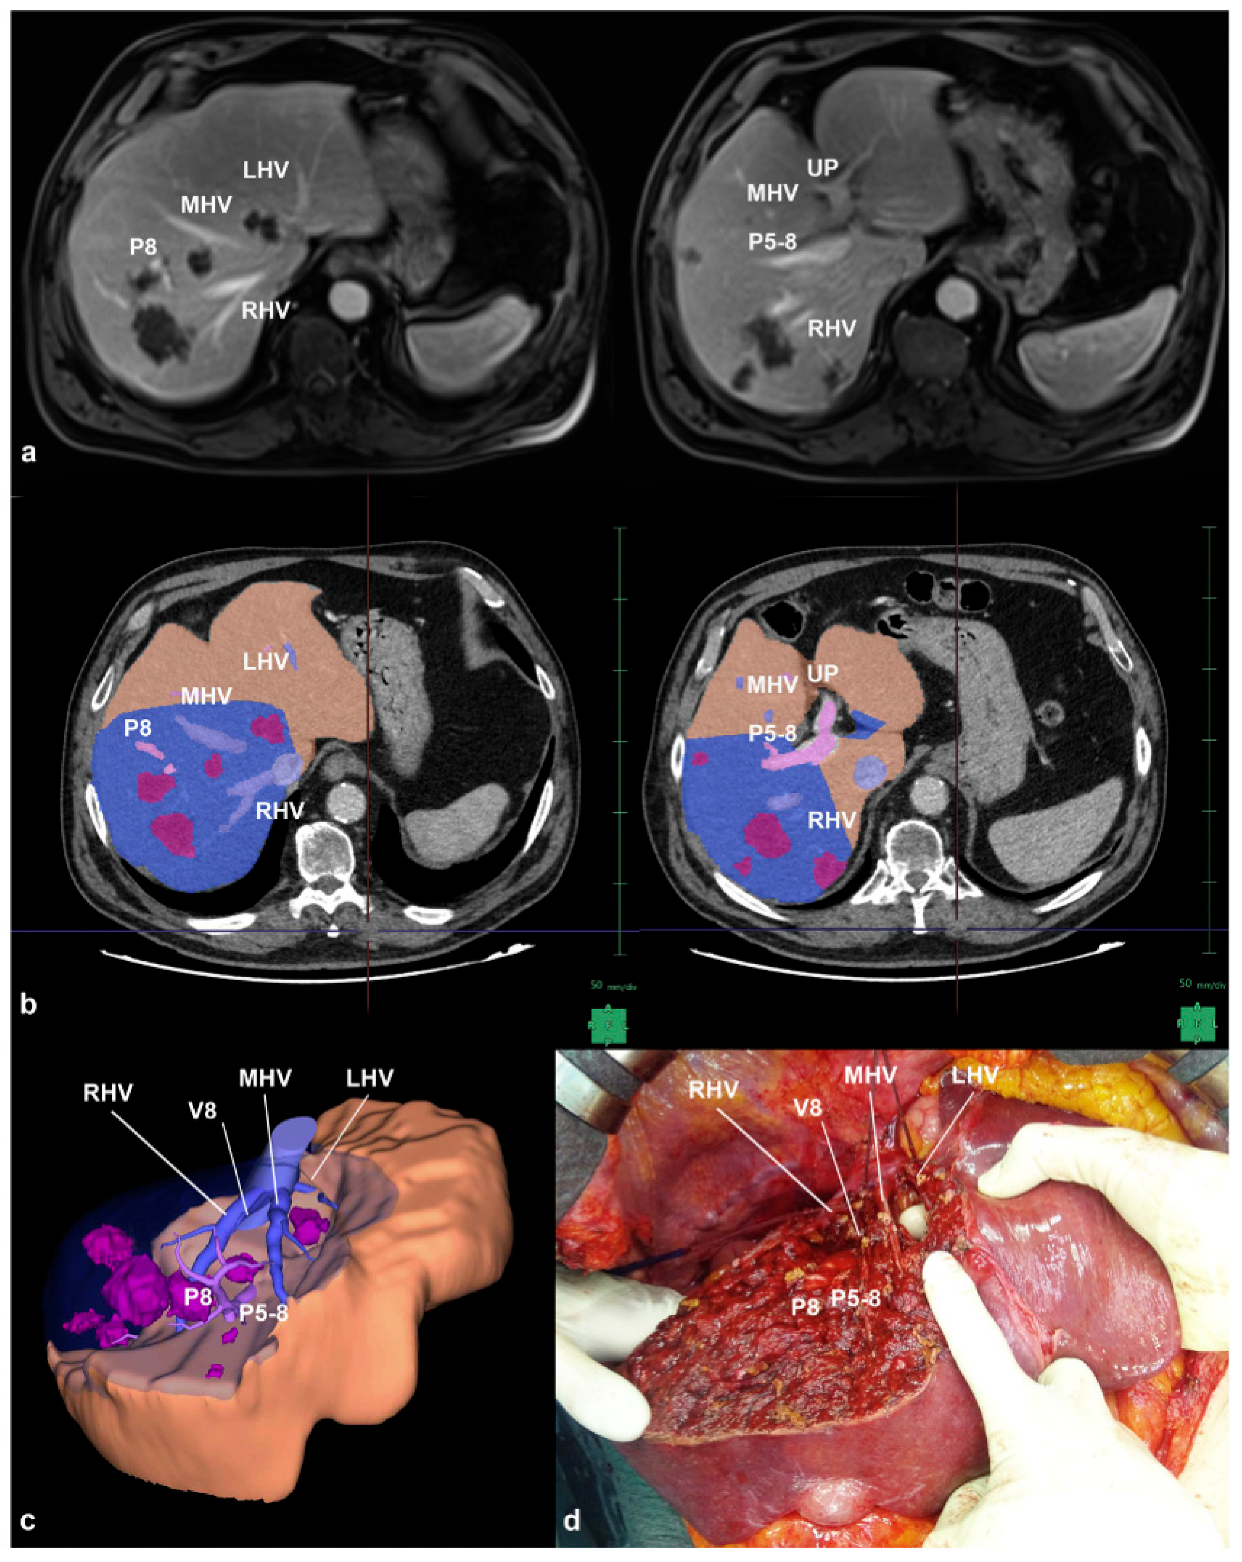

- Procopio, F.; Cimino, M.; Viganò, L.; Colombo, A.E.; Franchi, E.; Costa, G.; Donadon, M.; Del Fabbro, D.; Torzilli, G. Prediction of Remnant Liver Volume Using 3D Simulation Software in Patients Undergoing R1vasc Parenchyma-Sparing Hepatectomy for Multiple Bilobar Colorectal Liver Metastases: Reliability, Clinical Impact, and Learning Curve. HPB 2021, 23, 1084–1094. [Google Scholar] [CrossRef] [PubMed]